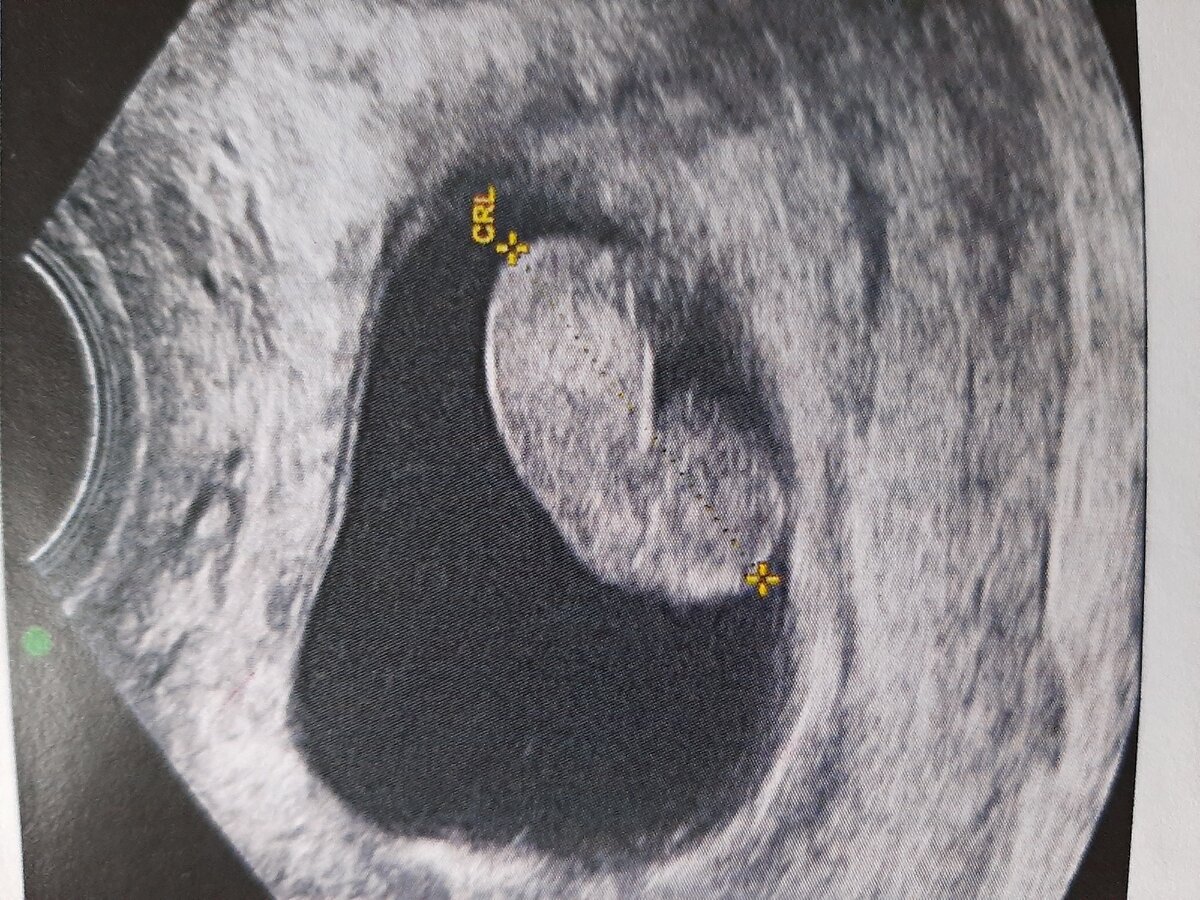

Увеличиваем изображение максимально, и измеряем копчико-теменной размер эмбриона ( КТР)

- максимальное изображение от головного конца до копчика. Именно это расстояние и позволяет нам определить срок беременности с максимальной точностью

Смотрите-какой красавчик!) Фото любезно предоставлено кафедрой лучевой диагностики

Срок беременности по КТР должен совпадать со сроком по ПЯ ( плодному яйцу). С минимальной разницей (1-3 дня). Если разница велика-повод насторожиться и пригласить женщину на дополнительный осмотр через 5-7 дней.